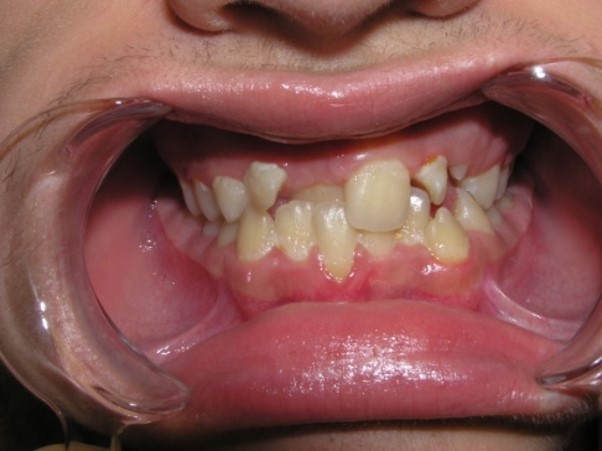

Palatal position of teeth is

characterized by the eruption of one tooth or a group of teeth outside the

dental arc on the palatal side. So, most often, incisors or second premolars

eruption.

(one or both) - 61.35%. In 57% of children, there are erased areas on the

incisal and vestibular surfaces of palatal-displaced teeth as a result of the

functional action of antagonist teeth. With a slight overlap, abrasion of the

cutting edge and shortening of the abnormally located tooth are observed. In the

palatal location of the upper jaw incisors, flattening of the frontal area of

the upper jaw and lengthening of the frontal area of the lower jaw are

determined. In this case, exposure of the necks of the lower frontal teeth,

violation of their stability and inflammation of the gums may be observed, and

the clinic of catarrhal or atrophic gingivitis develops as a result of

functional trauma.